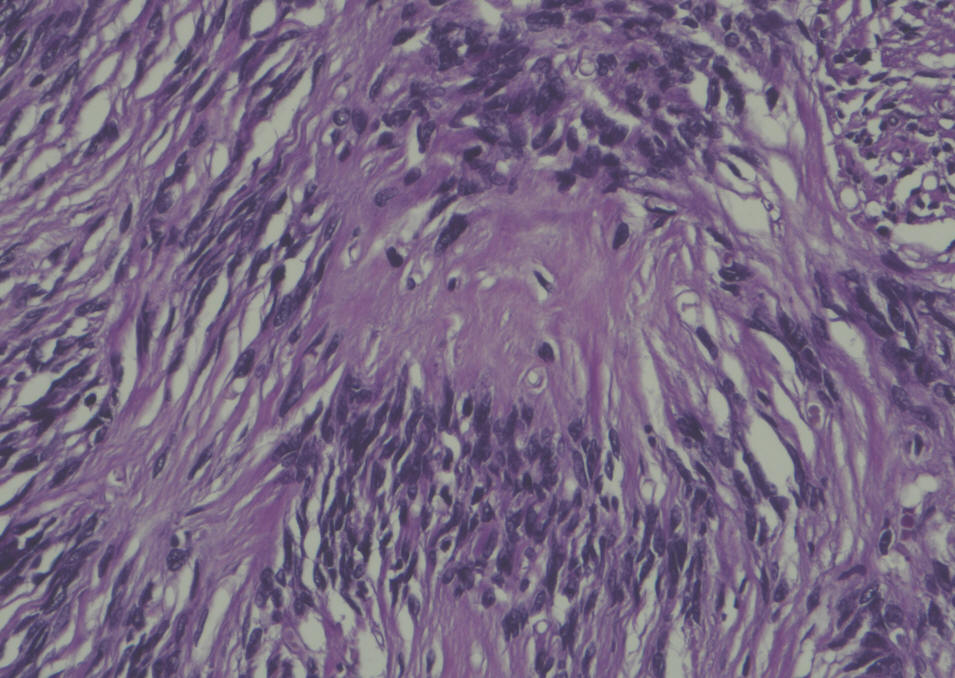

Sections show a circumscribed tumor composed of spindle cells displaying prominent nuclear palisading and Vercoy bodies. This lesion exhibits peripheral tongues extending into the brain cortical tissue. There is no evidence of mitotic activity, nuclear anaplasia or necrosis. Tumor shows heavy interstitial reticulin deposition and reacted positively to S-100 and Vimentin. Tumor did not react to GFAP and EMA. Proliferative index was estimated at 2%, but not exceed 3% in any area. There is no evidence of malignancy. Conclusion: Intracerbral schwannoma. ( Prof. Yahya F. Dajani Consultant pathologist. 29-January-2022.